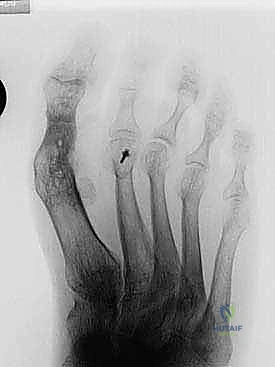

- التصوير بالأشعة السينية (X-rays): صور في وضعية الوقوف (تحمل الوزن) من زوايا متعددة لقياس زوايا التشوه بدقة وحساب مقدار الطول المفقود.

3. التشتيت وتحديد حجم الفجوة (Distraction)

باستخدام جهاز تشتيت متخصص (Distractor) أو ملقط جراحي، يتم سحب إصبع القدم برفق لإعادته إلى طوله الطبيعي ومحاذاته الصحيحة. يتم قياس الفجوة الناتجة بين العظم المشطي والسلامية بدقة بالمليمترات. هذا القياس يحدد حجم الطعم العظمي المطلوب.